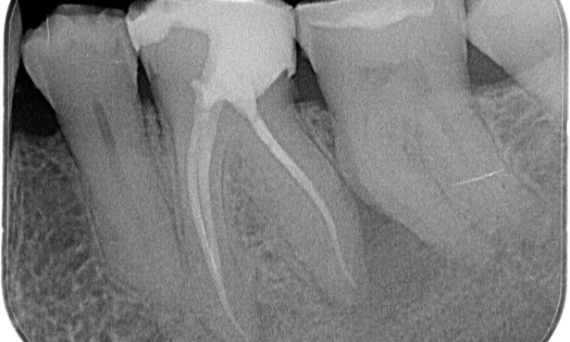

Antes: Radiotransparencia periapical asociada principalmente a la raíz distal y pérdida de la lámina dura en la raíz mesial.

Después: Se eligió TruNatomy en este caso para permitir un mejor abordaje de la caries y enfocarse en la conservación de la dentina pericervical, especialmente en el aspecto mesial, donde el diente presentaba una restauración más menor.

Bath, Reino Unido